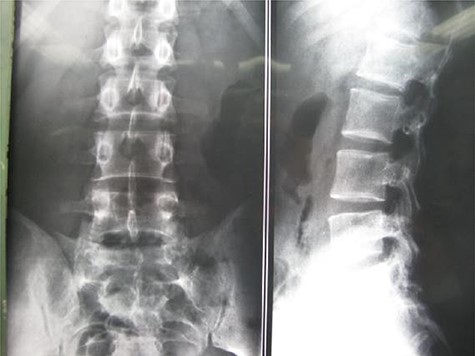

A 26-year-old male presented with pain over the lower lumbar area. Physical examination and laboratory tests were unremarkable with no neurologic deficit. X-ray and CT scans showed a lytic lesion with a sclerotic border in the right half of the body of the L5 vertebra (Figs 6 and 7). MRI showed a well-defined low signal lesion in T1 weighted images and high signal lesion in T2 weighted images (Fig. 8). The bone scan was negative. The patient underwent surgery and the lesion was extracted through the right pedicle and the remaining cavity was filled with an autologous bone graft from the iliac crest and right-side posterior fusion was done from L4 to L5 (Fig. 9). The pathology report was consistent with SBC. The patient had no recurrence seven years after surgery.

Case 2, Sagittal T2-weighted and T1-weighted MR images of lumbar vertebrae show the body and homogeneous cystic lesion of L5.